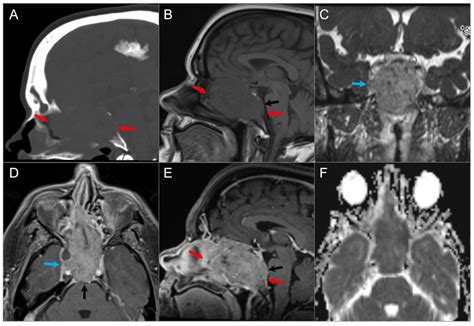

MRI (Magnetic Resonance Imaging) Provides high-resolution images of soft tissues, nerves, and the brain.

CT Scan (Computed Tomography) Highly effective at highlighting bony structures and identifying tumor-related bone erosion.